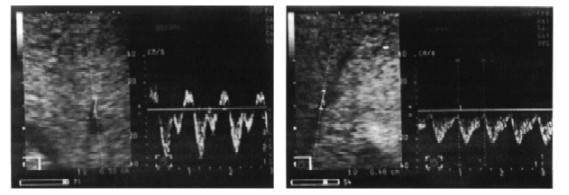

Следует заметить, что в зависимости от направления кровотока VА испытуемые разделились на 3 группы. В первой группе у 9 из 21 человека (суммарные данные в таблице 4) венозный отток стал монофазным, с исчезновением пульсирующего фазного характера его колебаний (рис. 11). Во второй группе (8 человек) сохранялся пульсирующий характер оттока, однако пропала фаза реверса в печень во время сокращения правого предсердия (рис. 12). В третьей группе (4 человека) кровоток в халасане оставался обычным, трехфазным. Отдельный обсчет результатов обследования в подгруппах с монофазным (М) и пульсирующим (П) печеночным оттоком крови во время позы "плуга" (см. таблицу 5) показал, что в исходном состоянии лиц с монофазным оттоком в момент упражнения отличали от других 8 испытуемых более низкая скорость притока по воротной вене Vp (21,0±2,0 и 27,7±1,3 см/с, p<0,05). Во время упражнения Vs при пульсирующем характере оттока была также выше, чем при монофазном оттоке (-31,4±4,1 и -19,5±2,9 см/с, p<0,05); при этом эти величины не изменились относительно их исходного уровня. Несмотря на то, что у ряда лиц с пульсирующим оттоком кровоток VА отсутствовал (отмечается прерывистый отток), в обеих подгруппах у большинства исследуемых поток крови поменял свое направление (p<0,01 - 0,001), но величина его в подгруппах существенно не изменилась (VА: П - -11,9±4,2 см/с, М - -9,6±1,0 см/с, p<0,05). Характерно, что различий по степени развившейся во время упражнения тахикардии мы также не обнаружили (ЧСС: М - 93,9±7,4 уд/мин, П - 95,2±8,3 уд/мин, p<0,05; между группами p>0,05). Изменений остальных показателей во время халасаны мы не наблюдали.

Рисунок 11. Развитие непульсирующего монофазного печеночного венозного оттока во время халасаны:

слева - исходное состояние, справа - во время выполнения упражнения

Рисунок 12. Развитие пульсирующего двухфазного печеночного венозного оттока во время халасаны:

слева - исходное состояние, справа - во время выполнения упражнения.